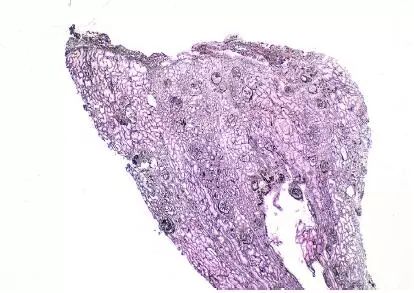

CNI肾毒性导致的血管收缩无形态学变化。急性CNI肾毒性特征包括:近端肾小管上皮细胞空泡化,大小一致;血管损伤,平滑肌细胞丢失;肌细胞胞浆空泡化;细胞坏死或凋亡退化。肌细胞损伤最终发展为局灶性结节性玻璃样变和透明样变,可延伸至小动脉和动脉血管壁整个中层。CNI肾毒性还可引起血栓性微血管病变(TMA),主要累及小动脉和肾小球毛细血管袢。慢性CNI毒性特征为:条状间质纤维化,肾小管萎缩。

图6 CNI肾毒性条状肾间质纤维化(Jones 银染)